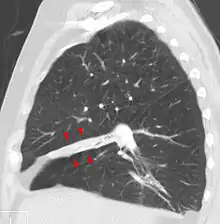

الانخماص الرئوي[1] أو همود الرئة[1][2][3] أو اللاتوسع الرئوي[3] من الكلمتين اليونانيتين (غير كامل: ἀτελής) و(امتداد: ἔκτασις) هو انهيار الحويصلات الهوائية في الرئة مما يؤدي إلى نقص أو غياب عملية تبادل الغازات. قد يحدث الانخماص لجزء من الرئة أو رئة كاملة.[4] حيث تكون فيه الحويصلات الهوائية فارغه من الهواء. و ما يميزه عن التصلب الرئوي هو أن انخماص الرئة تكون فيه الحويصلات الهوائية منكمشة.

من الشائع جداً اكتشاف الانخماص في صور الأشعة السينية للصدر وطرق إشعاعية أخرى، وقد يكون سببه الزفير الطبيعي أو العديد من الحالات الطبية، وعلى الرغم من كثرة وصفه على أنه انهيار أنسجة الرئة، فإن انخماص الرئة ليس مرادفاً لاسترواح الصدر وهي حالة أكثر تحديداً يظهر الانخماص كأحد اعراضها. الانخماص الرئوي الحاد ممكن أن يحدث بسبب مضاعفات ما بعد العمليات الجراحية أو نتيجة لنقص فاعل السطح الرئوي الذي يقلل من التوتر السطحي للرئة، وفي الاطفال حديثي الولادة هذا النقص يؤدي إلى متلازمة الضائقة التنفسية للرضع.

- الأشعة السينية للصدر (اعتِتَمام الرئة المصابة و تقلص حجمها)

- التصوير المقطعي

أشعة الصدر السينية كافية لتشخيص حالات الانخماض المعتدة اكلينيكياً. الانخماص ما بعد العمليات الجراحية يظهر في الجزء الأدنى من الرئتين.